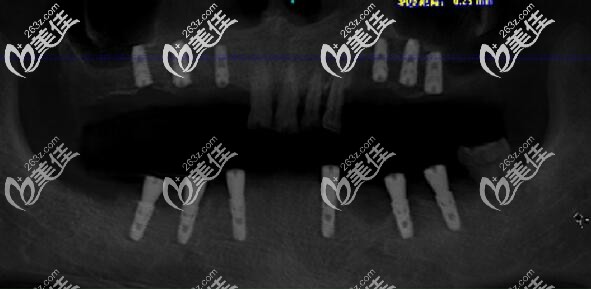

医生介绍:马建民,曾是医院种植科主 任,现在是南京美奥口腔(鼓楼)院长,从事口腔临床工作多年,拥有扎实的口腔基础知识理论功底和丰富的实践经验,擅长牙列缺损、牙列缺失的常规修复和种植义齿修复,尤其擅长各种骨量不足条件下的种植治疗。马院长在种植方面的高超技术,取决于他不懈的学习和钻研,除了经常参加种植新技术发布会,国内外口腔种植修复...